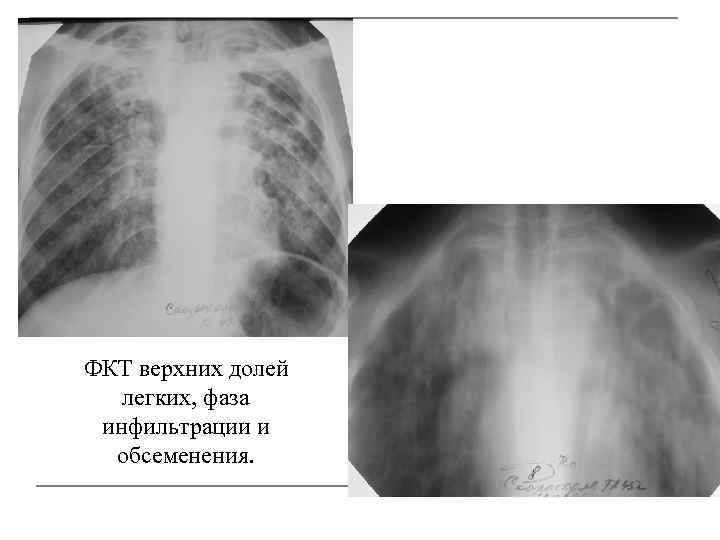

Симптомы и лечение инфильтративного туберкулеза легких

Раздел: Снимки-откровения